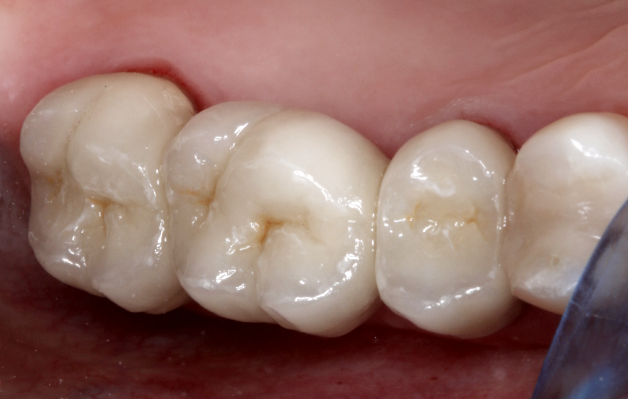

Amennyiben mindent rendben találunk a próbán (ahogy ezúttal is történt), nincs akadálya annak, hogy a fogpótlást stabilan rögzítsük (beragasszuk a helyére). Íme, a szép és tartós hídpótlás!

hídpótlás után